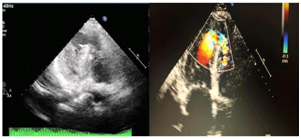

Angioplasty of the mid LAD was achieved successfully with 14'2mm .....stent. the VSR was crossed from the LV with a 6F cut pigtail and standard terumo wire 0.35 inch where it advanced into the pulmonary artery. A manually modified 6F multipurpose catheter was introduce through the internal jugular vein into the pulmonary artery where the terumo wire had been snared and exteriorized. A 20mm PIMVSD device (AGA medical) was advanced into the left ventricle and under transthoracic echocardiographic and continuous hand-injection through the already cutted pigtail into the left ventricle, the Figure 2 & Figure 3.

Figure 2 critical mid left anterior descending artery stenosis (A) that successfully managed with xience stent 2" 14mm (B).